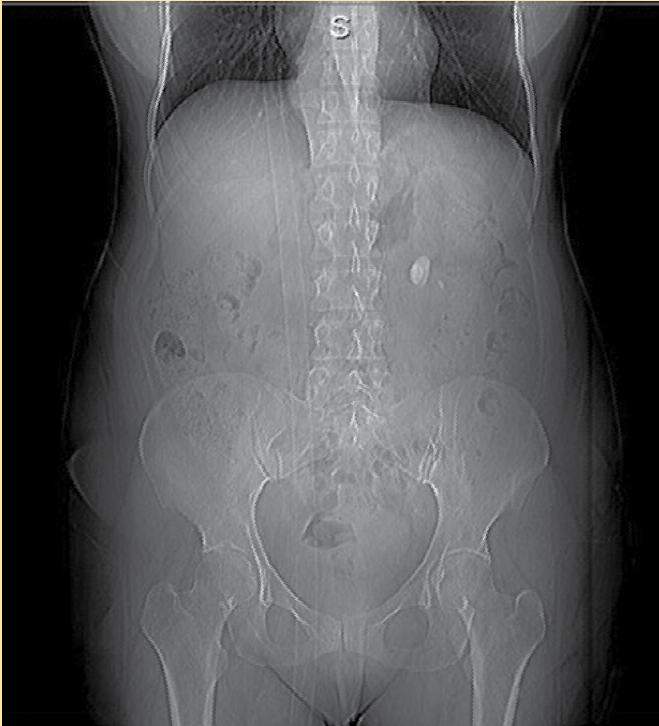

Se solicitaron exámenes paraclínicos de laboratorio completos que demostraron la presencia de leucocitosis a expensas de neutrofilia, con eritrocitos incontables por campo y cristales de oxalato de calcio regulares en el examen general de orina, con calcio sérico y niveles de paratohormona dentro de rangos normales. Se realizó una radiografía simple de abdomen que demostró la presencia de una imagen radiopaca. Dados los hallazgos se efectuó una urotomografía (UROTAC), y se apreció en el topograma una imagen redondeada radiopaca a nivel paravertebral izquierdo de L1 a L2 (Figura 1). En los cortes axial, coronal y en la reconstrucción tridimensional en fase simple y contrastada se hizo evidente una imagen hiperdensa en la pelvis renal izquierda con dimensiones de 2.19 × 1.54 × 2.58 cm e índice de atenuación de hasta 1762 unidades Hounsfield (Figura 2 3, 4), y se hizo el diagnóstico de litiasis piélica izquierda. Se inició impregnación antibiótica empírica previa toma de urocultivo y posteriormente se indicó tratamiento quirúrgico por medio de pielolitotomía laparoscópica izquierda. La evolución fue adecuada en el periodo postoperatorio. La paciente egresó al tercer día del postquirúrgico. Actualmente se encuentra en manejo multidisciplinario por endocrinología y urología, en espera del perfil metabólico para su adecuada categorización y tratamiento postevento lítico.

Figura 1 Topograma de urotomografía (UROTAC) con imagen paravertebral izquierda radiopaca a nivel L1-L2.